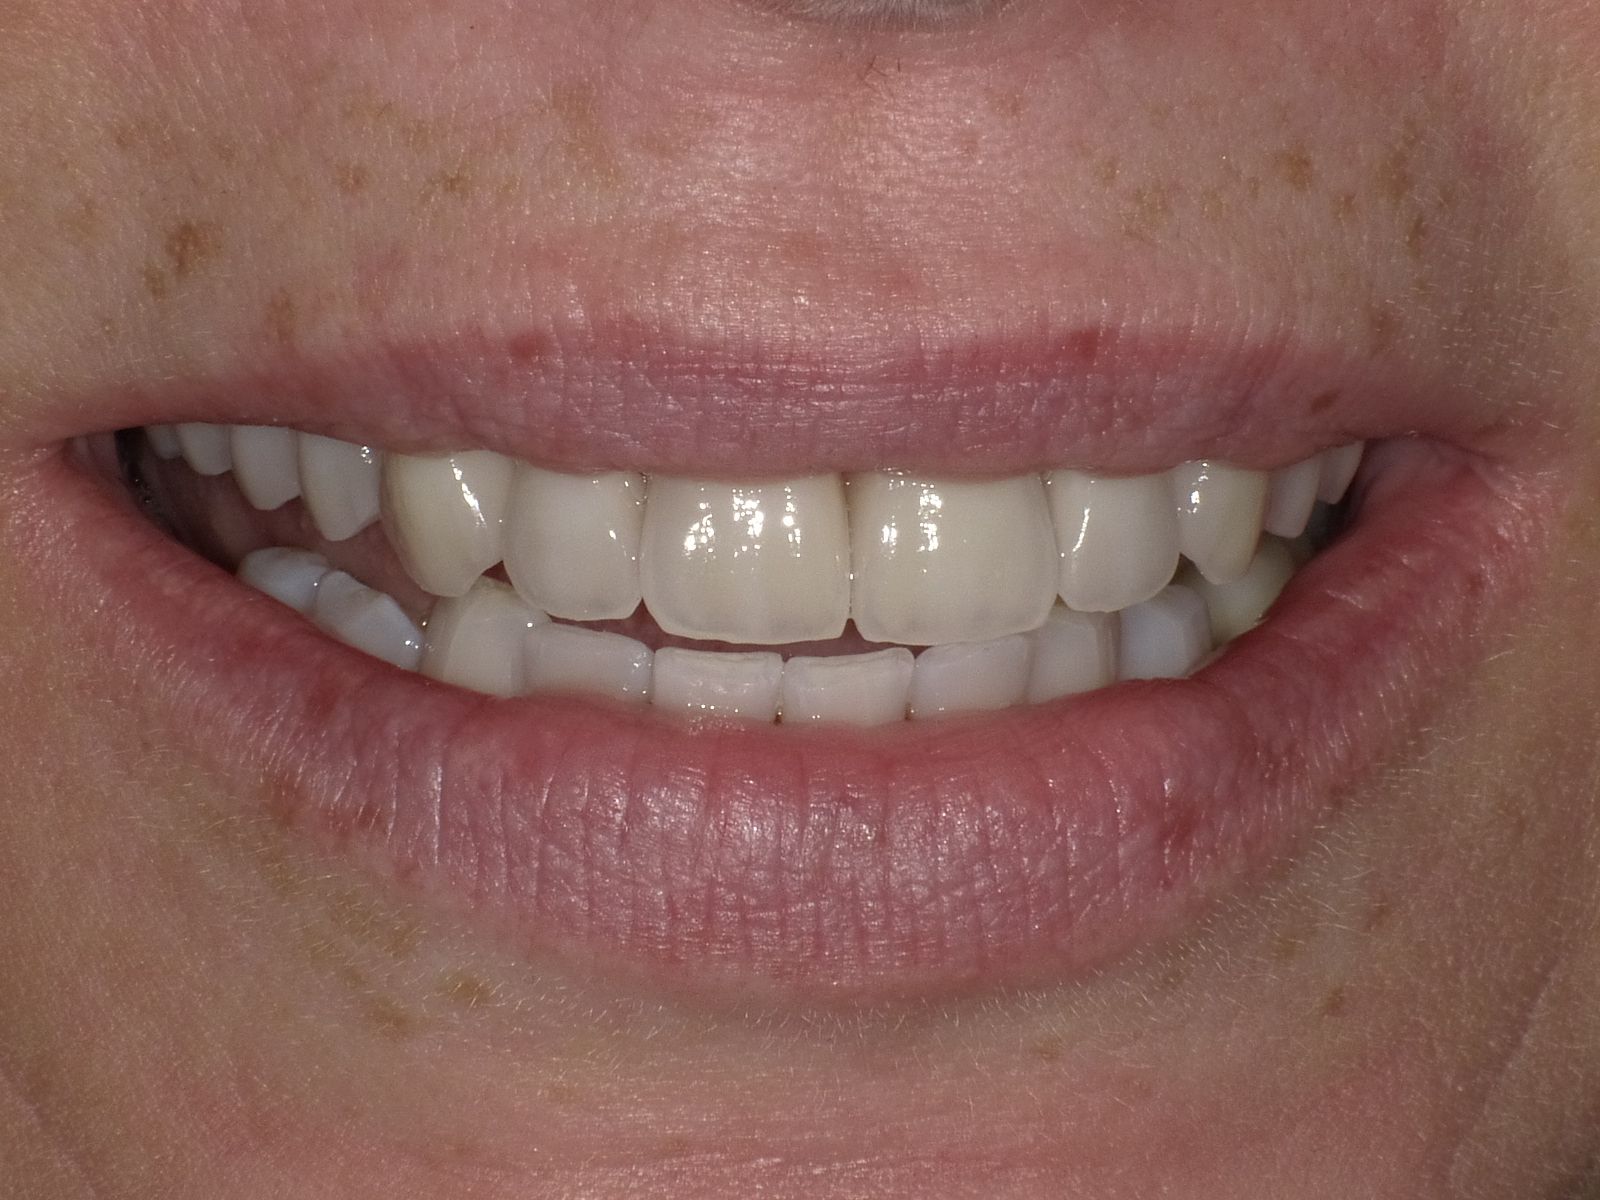

Diverse Vorbehandlungen mit für die Patientin absolut inakzeptablem Ergebnis

Vorher: Diverse Vorbehandlungen mit für die Patientin absolut inakzeptablem Ergebnis

Komplette Veränderung mit vollkeramischen Kronen und Veneers in nur 2 Langzeitterminen; auch hier nachher ganz anderes Auftreten der Patientin, die ihre Zähne jetzt gerne zeigt und wieder gerne lacht

Nachher: Komplette Veränderung mit vollkeramischen Kronen und Veneers in nur 2 Langzeitterminen; auch hier nachher ganz anderes Auftreten der Patientin, die ihre Zähne jetzt gerne zeigt und wieder gerne lacht